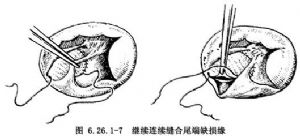

連續縫合補片修復法:由右房經三尖瓣口先於缺損12點部位,用4-0聚丙烯縫線做一單純縫合,補片修剪成略大於室間隔缺損(圖6.26.1-5),縫數針後拉緊縫線,將補片下送到位,繼續向頭端肌肉緣縫合(圖6.26.1-6左),牽拉縫線顯示下一步縫合區,抵達上方心室漏斗褶肌緣和三尖瓣環結合部後,縫線穿過三尖瓣前瓣基底部,自心室至心房側,隨後從心房回至心室側,穿過補片緣,收緊縫線(圖6.26.1-6右)。用另一頭縫線從缺缺損下緣往後繼續連續縫合(圖6.26.1-7左),到後下緣時縫線應離開缺損邊緣5mm,從間隔右室面進出針,切勿穿過間隔組織,以防損傷希氏束(圖6.26.1-7右)。兩針於相遇處結紮,閉合缺損。